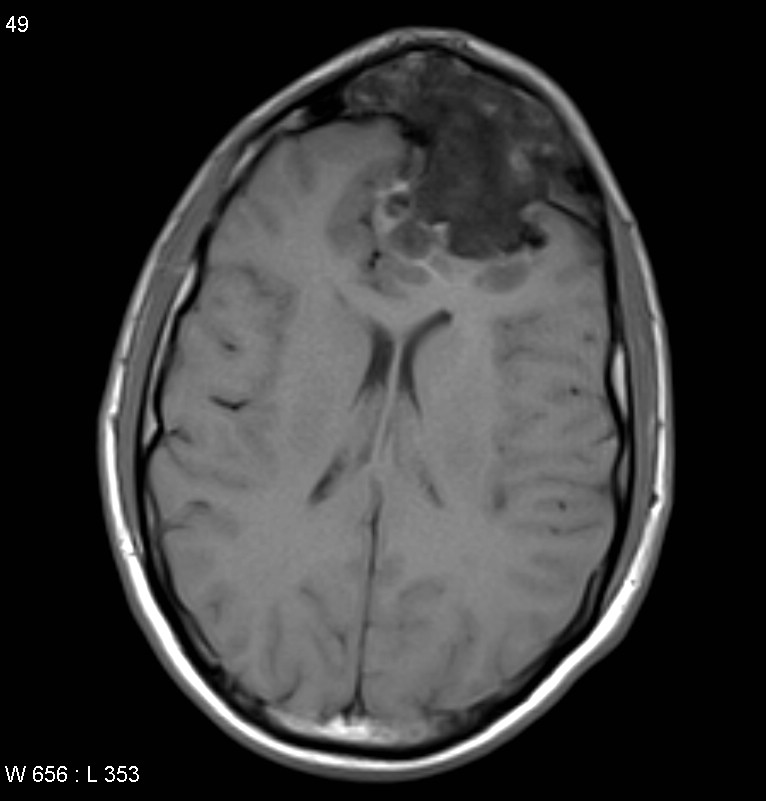

Lésion maligne du sinus frontal droit

Les tumeurs malignes

Elles sont heureusement rare. La plupart du temps il s’agit de tumeurs provenant d’une autre zone des fosses nasales mais dont la progression atteint le sinus frontal ( adénocarcinomes de l’ethmoïde, carcinome épidermoïdes, esthésioneuroblastomes……).